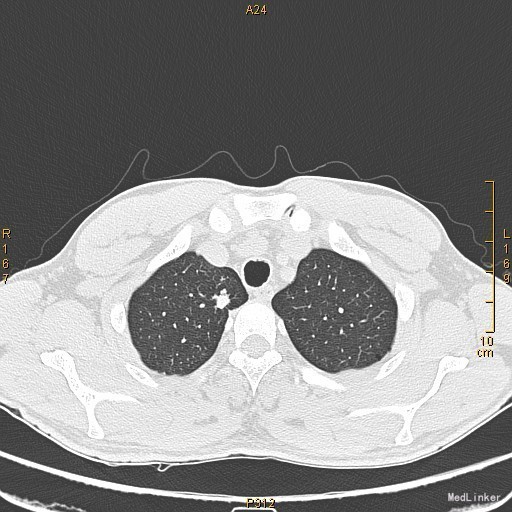

主诉:左眼睑下垂1年,加重半年。病史:患者1年前无明显诱因出现左眼睑下垂,抬起困难,伴视物重影,无言语不能、吞咽困难,无发热、头痛、恶心、呕吐、头晕、视物旋转、肢体麻木、饮水呛咳、视物模糊、肢体不自主运动、肢体抽搐、意识障碍、大小便失禁,休息后缓解,未予重视,半年来上述症状反复加重,10余天前至当地医院就诊,查新斯的明试验阳性,遂至我院神经内科就诊,胸部CT示:1、右肺尖钙化结节;2、胸腺增生。为了进一步治疗门诊拟“重症肌无力”收住我科。患者自起病以来,无发热、咳嗽、尿频、尿急、腹泻,无心悸、胸闷等,精神、食欲、睡眠好,体重无明显变化。

查体:左侧眼睑下垂,右侧眼裂宽10mm,左侧眼裂宽5mm。肺部查体未见异常。 辅查:新斯的明试验阳性。胸部CT示1、右肺尖钙化结节;2、胸腺增生。

该患者诊断“1.重症肌无力,眼肌型;2.右上肺钙化结节”明确,重症肌无力合并胸腺增生或胸腺瘤,有手术指征,我们为患者行胸腔镜下胸腺扩大切除术+右肺上叶楔形切除术。术后病理示:右上肺结节呈干酪样坏死,考虑结核。胸腺及纵隔脂肪均见淋巴增生。术后效果明显,患者左侧眼睑下垂较前好转,右侧眼裂宽10mm,左侧眼裂宽8mm,视物重影症状消失。